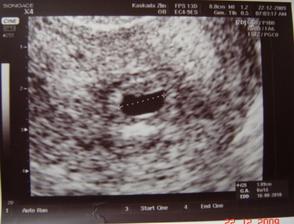

-10.12 hcg 130iu

-22.12 hcg 8000iu

29.12 krvacení a následna hospitalizace - hematom

20.1 KO na rizikovém vše v pořádku hematom se zmenšuje ale musím ležet důležité je že je prcíček v pořádku

17.2 NT screening - negativní hurá vše je v pořádku prcík měří 7,4cm a je to nejspíš holčička takže naše malá MAGDALÉNKA

-12.4 velký UTZ potvrzeno je to holčička je v pořádku měří jak má ale zjištěno malo plodové vody a ztluštěna stěna placenty hematomního vzhledu (chjooo já snad nebudu mít klid do porodu) kontrolní velký ultrazvuk za 14 dní

-28.4 kontrolní velký ultrazvuk Tak jsem doma s ultrazvuku a vše je v pořádku plodovky je normální množství a hematom tam není placentu mám prý na zadní straně vysoko tak ze začátku byla pořád na přední straně nizko naposled byla na zadni stěně nízko a ted už je vysoko tož jsem s toho jelen 🙂 hlavně že je vše v pořádku 🙂 a je to teda opravdu holčička nic se nezměnilo pindík nedorostl 🙂